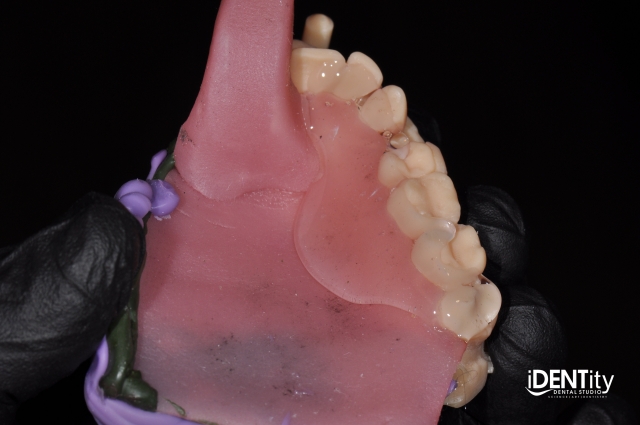

3. A maxillary baseplate/custom tray was used to capture the lateral extent of the right maxilla and posterior defect, utilizing border molding compound and VPS bite registration material.

BrandonStapleton hybrid digitalanalog technique for maxillofacial prosthodontics Fig.2